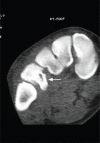

Figure 3:

Figure 3:. CT scan of the right foot showing lytic lesion (arrow)